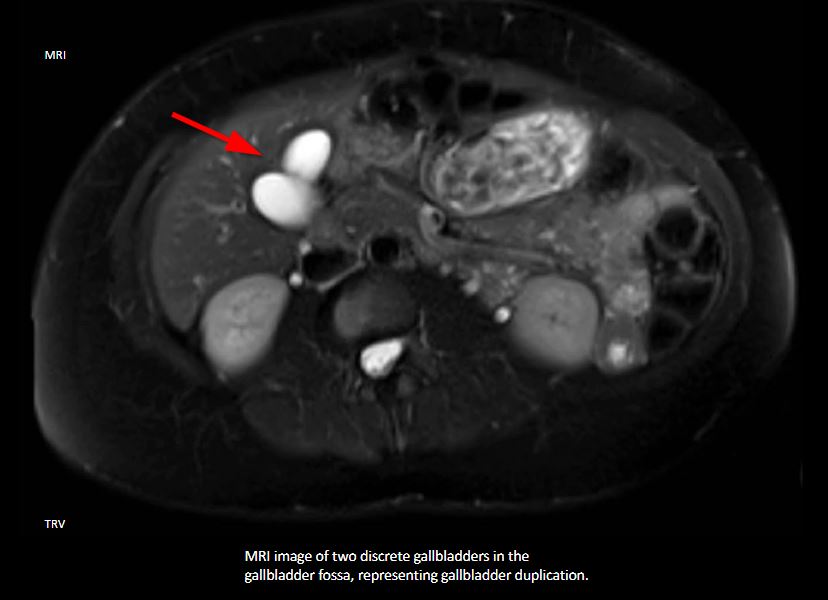

n ultrasound, duplicated gallbladder presents as two discrete adjacent gallbladder lobes as opposed to a single oblong vesicle. Sonographic evaluation of the gallbladder is considered the most helpful and highly sensitive diagnostic tool in assessing gallstones, cholecystitis, and other gallbladder conditions. However, in the setting of the duplicated gallbladder, ultrasonography may not completely differentiate it from other conditions such as Phrygian cap or choledochal cyst. Also, differentiation of the specific type of duplication is typically not possible with ultrasound alone since even with current real-time equipment, the cystic duct is challenging to identify. CT and MRI are more effective imaging techniques to confirm the diagnosis and delineate the classification type of suspected gallbladder duplication